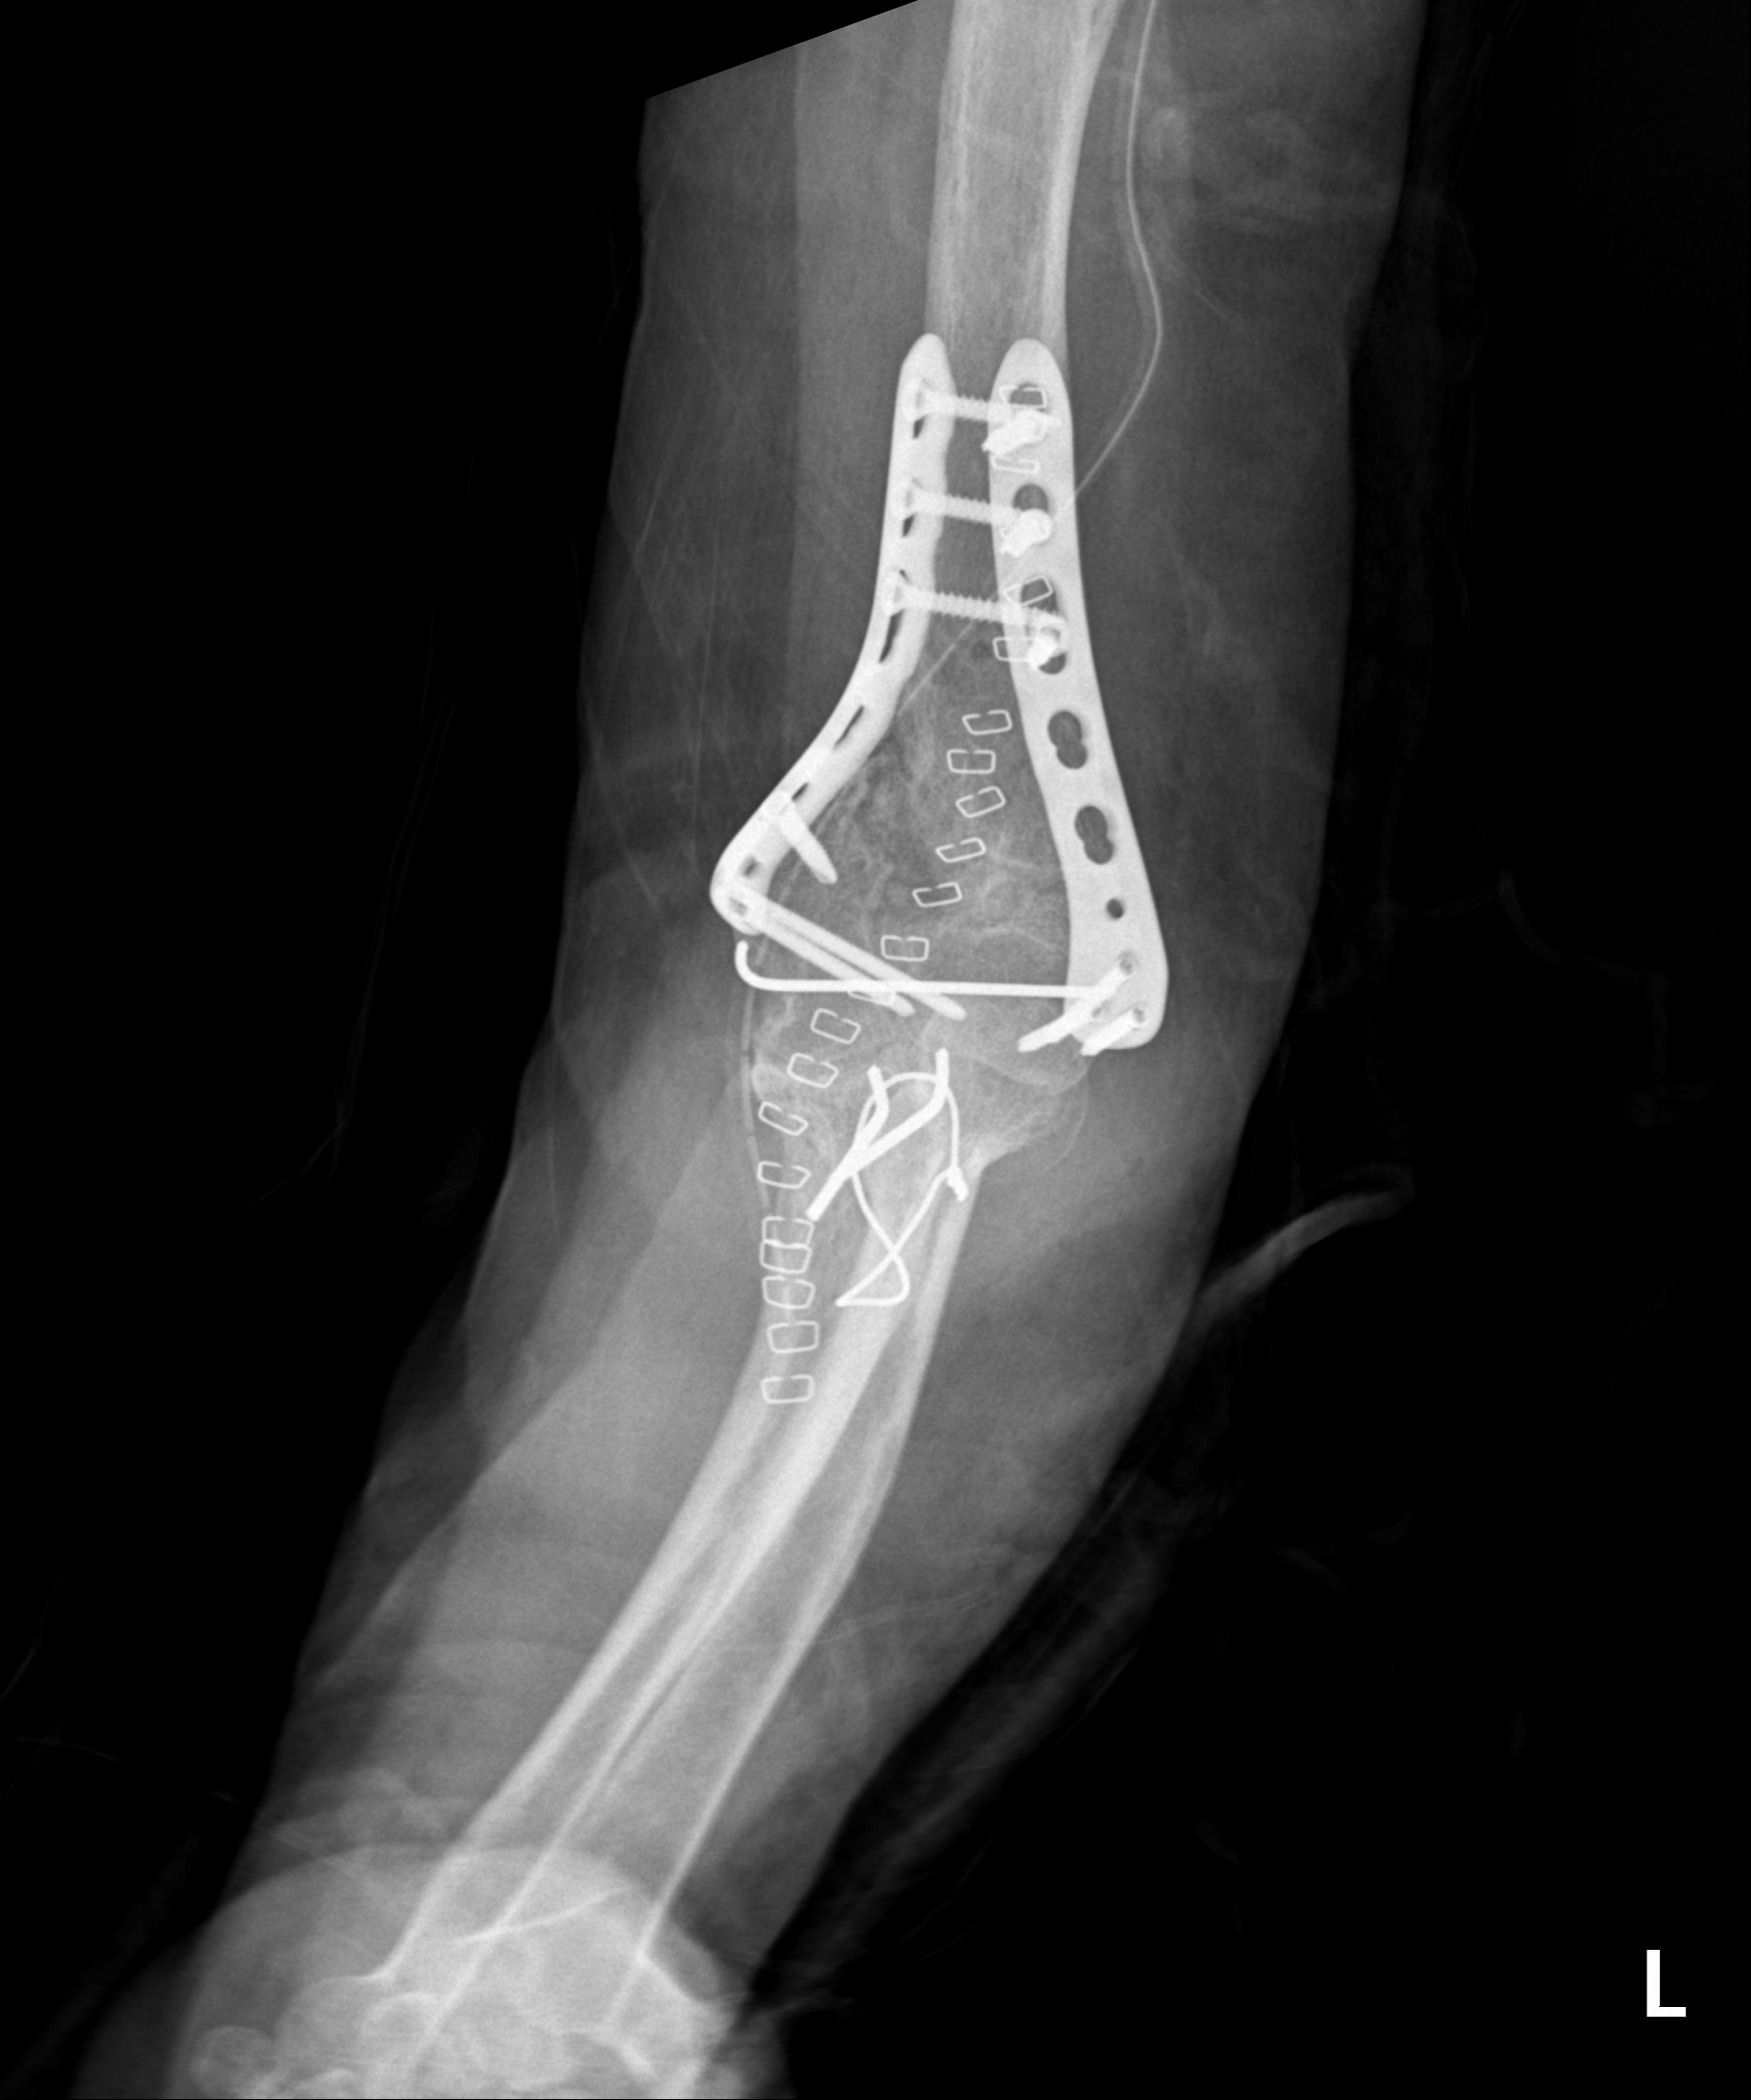

원위 상완골 골절

2022.07.14

2023.02.07